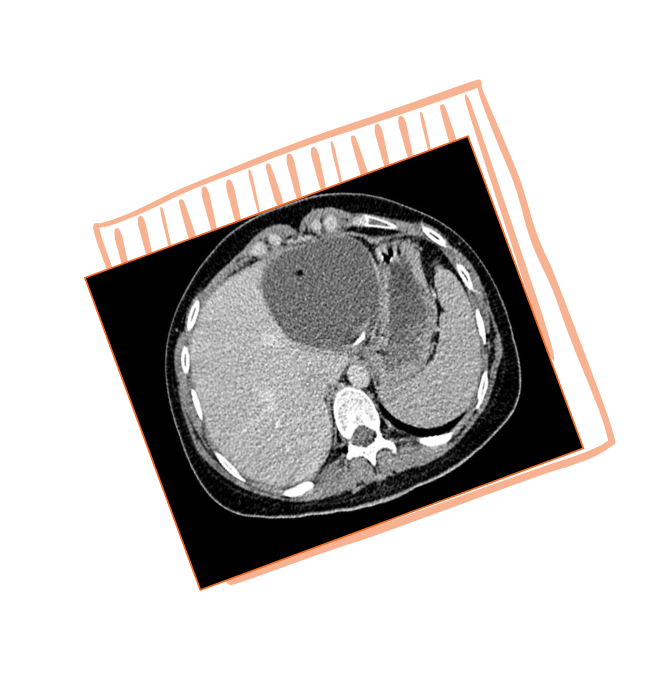

КТ брюшной полости и малого таза:

В печени выявляются гиподенсные очаги: субкапсулярно

в С7/6 печени 50х25мм, в С6 — 44х38мм, в С5 — 11х9мм,

с С7 — 11х7мм, в С3 — 15х14мм